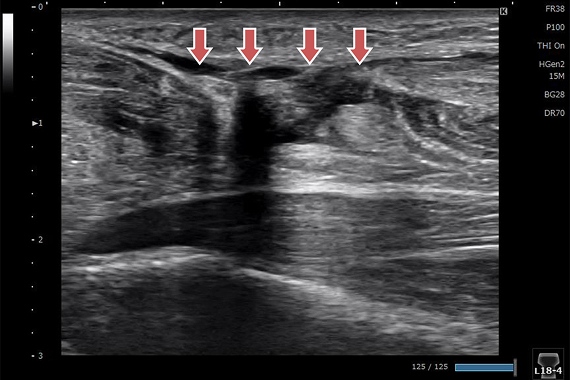

野球肘

左右を比較すると離断性骨軟骨炎の所見がはっきりわかります。